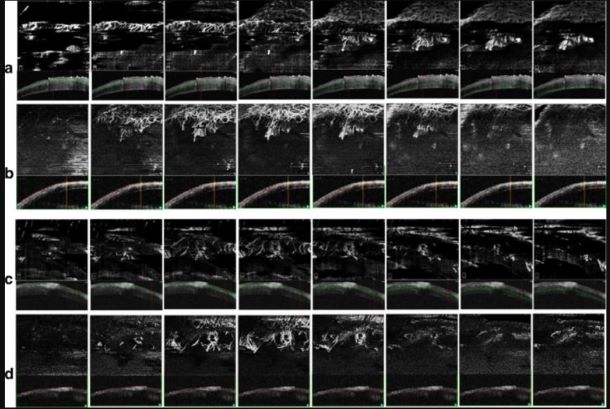

正面OCTA分割图像的比较。图示了对于图1a中在第2周随访时间点成像的OCTA图像,在SSADA OCTA系统中每50μm深度处对OMAG OCTA系统执行的正面和相应的横截面分割。图1b在第1周的随访时间点的类似分割图如图2c所示,使用SSADA OCTA,图2d使用OMAG OCTA。SSADA横截面B扫描中的分割线标记为绿色,而OMAG B扫描中的分割线则标记为红色。 如图2a和c所示,从表层投射的SSADA OCTA在较深层分割的正面图像中存在血管。

使用数字裂隙灯相机在标准漫射照明下捕获彩色SLP图像。图1在第1周和第2周在相同感兴趣区域的时间点期间拍摄的具有代表性的OCTA图像。从两个系统的每个OCTA中提取在角膜B扫描每50μm处分割的相同代表性图像,并进行比较,如图2所示。SSADA系统中的分割算法是基于黄斑B扫描层分割的,而OMAG OCTA分割是基于为研究目的而开发的自定义并行层分割的。